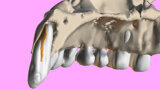

Fig. 1: The patient presented with a horizontally fractured clinical crown, an indication for a partial extraction therapy procedure.